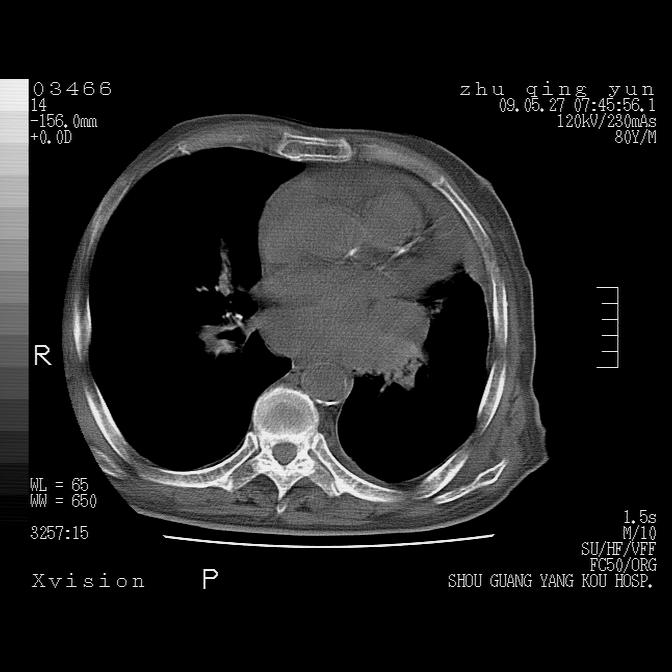

病人男性,年龄80,气喘来院,其他病史不太详细,1月前有过恶心,呕吐,在当地人民医院做过钡餐,诊断胃炎,

1)考虑左肺中央型肺癌并阻塞性肺炎,后下纵隔受侵伴纵隔淋巴结转移。2)双侧少量胸腔积液,胸膜增厚。3)心包积液。

左肺下叶见多发片状及结节状病灶,左肺基底段支气管闭塞,纵隔内见多发淋巴结肿大,纵隔向左侧移位,左侧胸廓变小。应该是左肺下叶中心型肺癌,纵隔淋巴结转移,左侧肺内转移,左肺基底段肺不张,阻塞性肺炎。

1)考虑左肺中央型肺癌并左肺下叶阻塞性肺炎、不张;左胸膜腔积液、心包积液、纵隔淋巴结转移;癌肿累及左心房。2)左心室大。冠状动脉壁钙化斑。